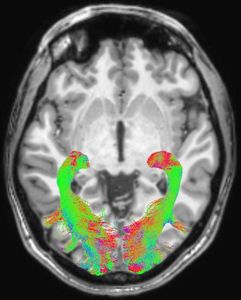

Gehirn-Scan: Strukturen verändern sich frühzeitig (Foto: rsna.org) |

20 neu diagnostizierte und noch nicht behandelte Patienten nahmen an der Studie teil - elf Männer und neun Frauen. Die gesunde Kontrollgruppe war gleich groß. Ein MRT wurde bei allen Teilnehmern durchgeführt. Bei den Patienten fand sie innerhalb von vier Wochen nach der Diagnose statt. Die Forscher verwendeten dabei eine diffusionsgewichtete Bildgebung, um Veränderungen der weißen Substanz und die voxel-basierte Morphometrie, um Konzentrationsveränderungen der grauen und weißen Substanz zu untersuchen.

Bei den Parkinson-Patienten zeigten sich signifikante Anomalien in den Gehirnstrukturen des visuellen Systems. Dazu gehörten Veränderungen der Sehstrahlung, eine Verringerung der Konzentration der weißen Substanz und eine Reduktion des optischen Chiasma. Im letztgenannten Bereich kreuzen sich die rechten und linken Sehnerven.